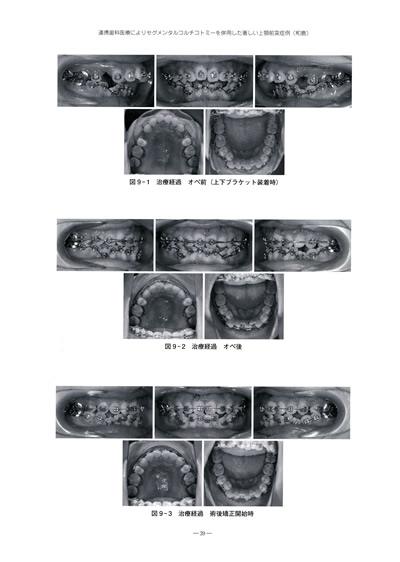

連携歯科医療によりセグメンタルコルチコトミーを

併用した著しい上顎前突症例(和島)